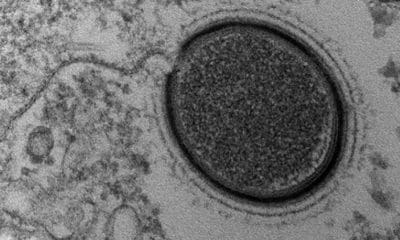

¿Y si todo lo que supiéramos acerca del VIH fuera sólo una gota de agua en medio del océano? Una nueva investigación publicada en Cell Reports muestra un mecanismo tan...